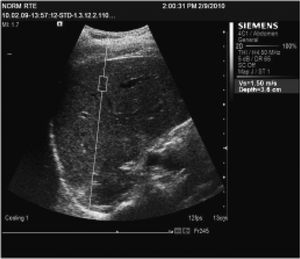

Spleen and liver stiffness evaluation by means of ARFIIn each patient was measured LS by means of ARFI in the right liver lobe, 1-2 cm below the liver capsule, by intercostal approach, with the patient laying in left lateral decubitus (Figure 1). SS was also assessed by means of ARFI, 1-2 cm under de spleen capsule, by intercostal approach, with the patient laying in right lateral decubitus (Figure 2). Scanning by means of ARFI was performed with minimal scanning pressure applied by the operator, while the patients were asked to stop breathing for a moment, in order to minimize breathing motion. ARFI measurements were performed with a Siemens Acuson S2000™ ultrasound system. In each patient 10 valid ARFI measurements were performed both in the liver and in the spleen and median values were calculated, the results being expressed in m/s.

Ultrasound examinationThe ultrasound examination was performed in each patient in the same session with ARFI measurements using a Siemens Acuson S2000™ ultrasound system, with a convex array probe of 4-9 MHz. The antero-posterior diameter of the spleen was measured and considered to be indicative of the spleen size. The patients were evaluated also for focal liver lesions, portal vein thrombosis, presence of ascites.